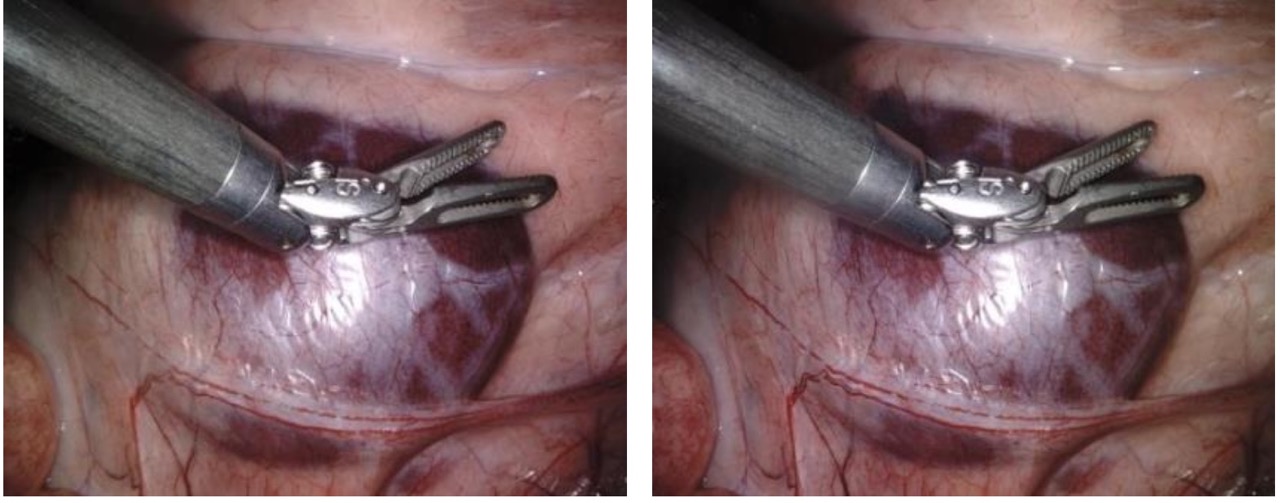

This component focused on reconstructing 3D structure from stereo endoscopic images of a surgical scene:

- Salient Features: Identified keypoints with strong geometric distinctiveness across stereo pairs to support reliable correspondence.

- Stereo Matching: Matched features between stereo views and filtered outliers based on geometric consistency.

- Fundamental Matrix Estimation: Derived the epipolar geometry governing the stereo image pair to constrain valid correspondences.